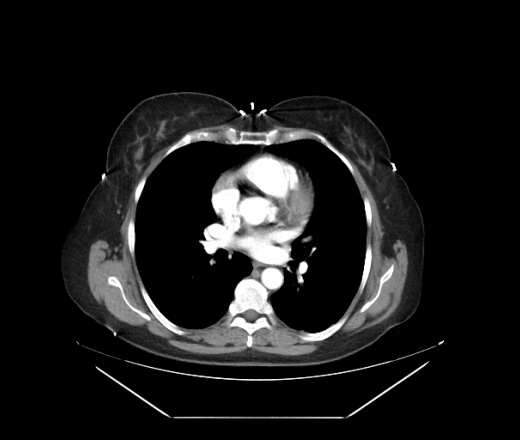

Женщина направлена по поводу кист левой почки, подготовка к перативному лечению. Случайная находка в правой доле печени: два подкапсульных образования с обызвествлением стенки, и очаг понижения плотности визуализирующийся только в венозную фазу.

...и очаг понижения плотности визуализирующийся только в венозную фазу - гемангиома. ...два подкапсульных образования с обызвествлением стенки - одно мне кажется вообще не в печени а рядом, другое - прогностического значения не имеет - типа кальцинат..